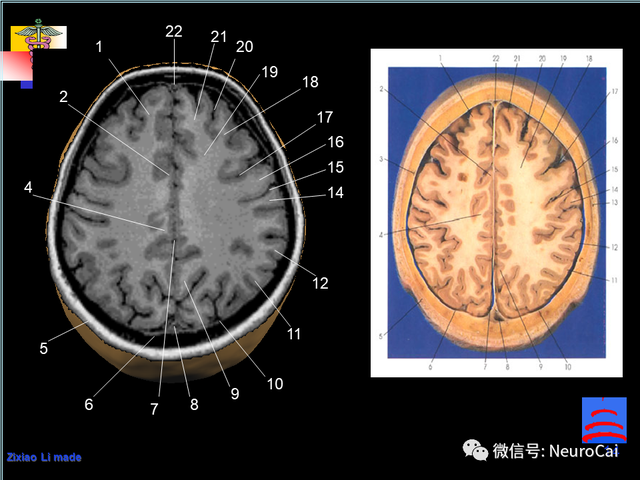

大脑结构图及功能图,人类大脑十大三维解剖图(脑局部解剖与功能图谱)